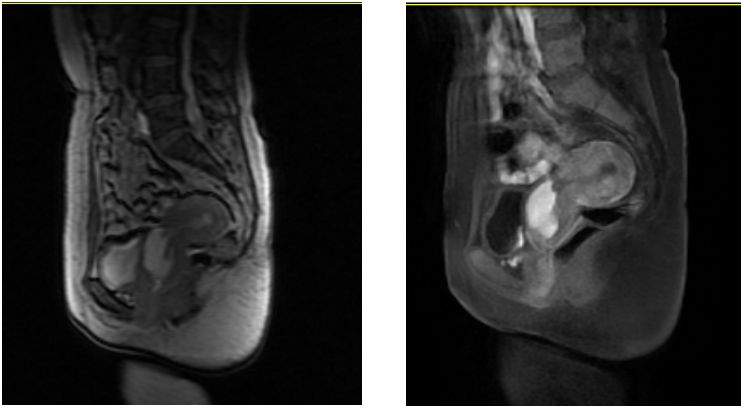

2019-12-30本院经阴道三维子宫附件超声检查示:子宫后位,正常大,内膜厚0.9cm(双层)。前峡部见4.0*3.1cm液性暗区,与宫腔相通,内液稠,宫腔内见多个偏强回声,较大约位于下段1.0*0.9*0.3cm,内见血流。余宫壁回声均匀。双卵巢正常大,回声无殊。右卵巢内见1.8*1.3*2.0cm囊性回声,内液稠。诊断结果:子宫正常大,前峡部暗区(合并内异病灶待排),宫腔多发偏强回声(息肉考虑),右卵巢内囊性块(内异囊肿考虑)。

2020-01-03本院盆腔MRI增强扫描示:子宫峡部-宫颈管见大小约4.2cmx3.6cmx2.9cm囊性肿块,边界清楚,内部可见分隔及分层样改变,增强扫描未见明显强化,局部肌层厚约0.2cm。右侧卵巢内见1.4cmx1.6x1.2cm类似信号影。子宫内膜厚约0.55cm,信号不均,增强扫描未见宫腔内异常强化影。左侧卵巢大小及信号未见明显异常。盆腔淋巴结未见明显肿大。盆腔少量积液。诊断结果:1.子宫峡部-宫颈管内囊性灶,考虑内异囊肿。2.右卵巢内异囊肿。3.子宫内膜信号不均,请结合临床。